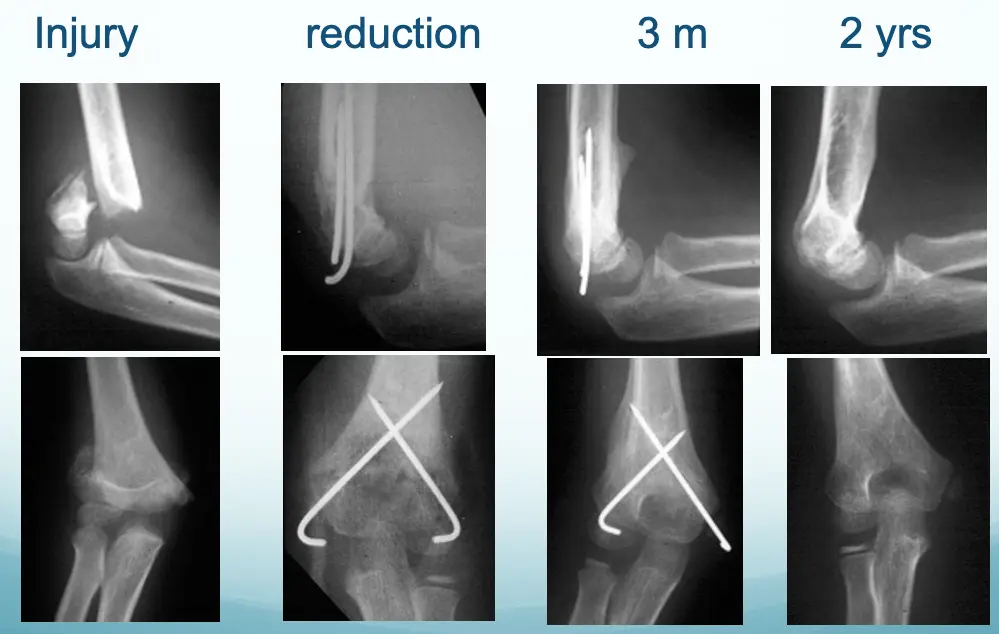

Case Example: 6-year-old girl, fell from swing

Initial injury

After reduction

3 months follow-up

2 years follow-up